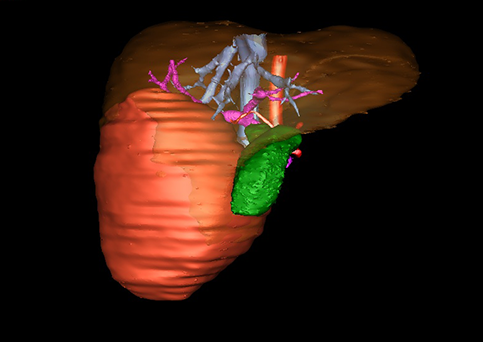

近年来由于数字医学的发展,基于可视化三维重建技术的计算机辅助手术系统极大推进了小儿肝脏肿瘤的精准手术的进步。可以立体透视肝脏解剖、精确掌握肝段的边界、精确测算肝段乃至任意血管所支配的功能体积、准确定位病灶及其与邻近血管的解剖关系,最终对不同手术方案进行比较、筛选和优化。因此,计算机辅助手术规划系统是实现精准肝切除的有力辅助工具,是未来数字外科、精准外科等21世纪外科新理念的重要技术支撑。

计算机辅助手术规划系统具有良好的操作可行性、计算准确性和三维显示效果,可半透明、交互式显示真实的肝内立体解剖关系和空间管道变异,准确计算肝内管道的直径、走行角度,两点间的垂直距离,和任意血管的支配或引流范围等传统二维影像无法获取的信息,有助于实施个体化手术,提高了手术的确定性、预见性和可控性。计算机辅助手术规划系统可直观显示预留肝脏的结构和功能,并可通过虚拟切割功能辅助术者对手术方案进行蹄选和优化,系统评估手术风险和制定对策,改变了部分二维规划的术式和切除范围,使部分二维规划认为不能切除的患者成功手术,提高了手术的根治性、安全性和病变的可切除性,更加符合精准肝脏外科的术前规划要求。详见第11章。

随着计算机技术及影像检查技术的不断发展,以精确的术前影像学和功能评估、精细的手术操作为核心的精准肝切除技术日益受到重视。基于数字医学的计算机辅助手术技术(computer-assisted surgery,CAS)则是实现肝脏精准手术操作的基础。计算机辅助手术系统(CAS)可将术前二维(two dimensional,2D)的CT/MRI影像数据进行三维(three dimensional,3D)重建,建立个体化的肝脏三维解剖模型,清晰显示肝脏内脉管系统的走行及解剖关系,还原病灶与其周围脉管结构的立体解剖构象,准确地对病变进行定位、定性和评估,制定合理、定量的手术方案,实施个体化的肝脏血管取舍分配方案及实施精准肝脏手术。一般认为CAS包括:创建虚拟的患者的图像;患者图像的分析与深度处理;诊断、手术前规划、手术步骤的模拟;术中实时导航。应用本技术后,由于可以更清晰地看出肿瘤的界限,特别是根据肝血管的显影,判断出肿瘤与门静脉及肝静脉的关系以在手术前较准确地估计出手术成功切除的可行性。以往部分根据普通强化CT判断无法手术的病例而被评估为可以成功切除并手术成功。